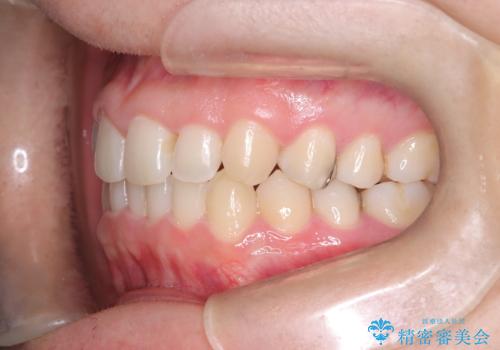

前歯のガタつきと逆の噛み合わせを、短期間のインビザラインで改善

- 前歯の叢生(ガタつき)と、上下の噛み合わせが一部逆になっている反対咬合を主訴にご来院されました。精密検査の結果、前歯の移動だけでは不十分で、歯列全体のアーチを整えながらスペースを確保する必要があると診断。

中等度の症例に最適で最大26ステージ(※プランによる)のマウスピースが使用可能な**「インビザライン・モデレート」**を選択しました。これにより、抜歯をせずに歯列を横に広げ(側方拡大)、前歯を並べる十分なスペースを作りながら反対咬合を確実に改善する計画を立案しました。

反対咬合の解消: 内側に入っていた前歯を、マウスピースの力を利用して外側へ押し出しました。同時に、下顎の歯並びも微調整することで、スムーズに正常な噛み合わせへと誘導しました。